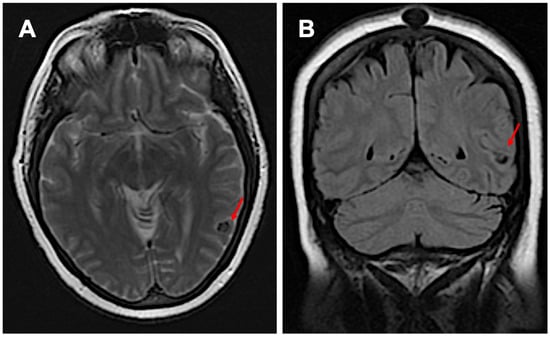

2. Case Presentation